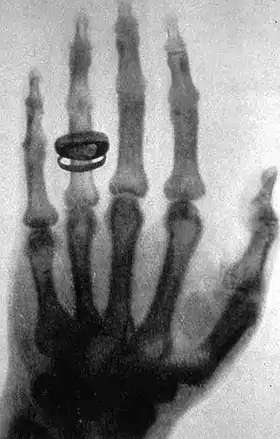

His hand was one of the first to be x-rayed, by his friend Wilhelm Roentgen.[3]